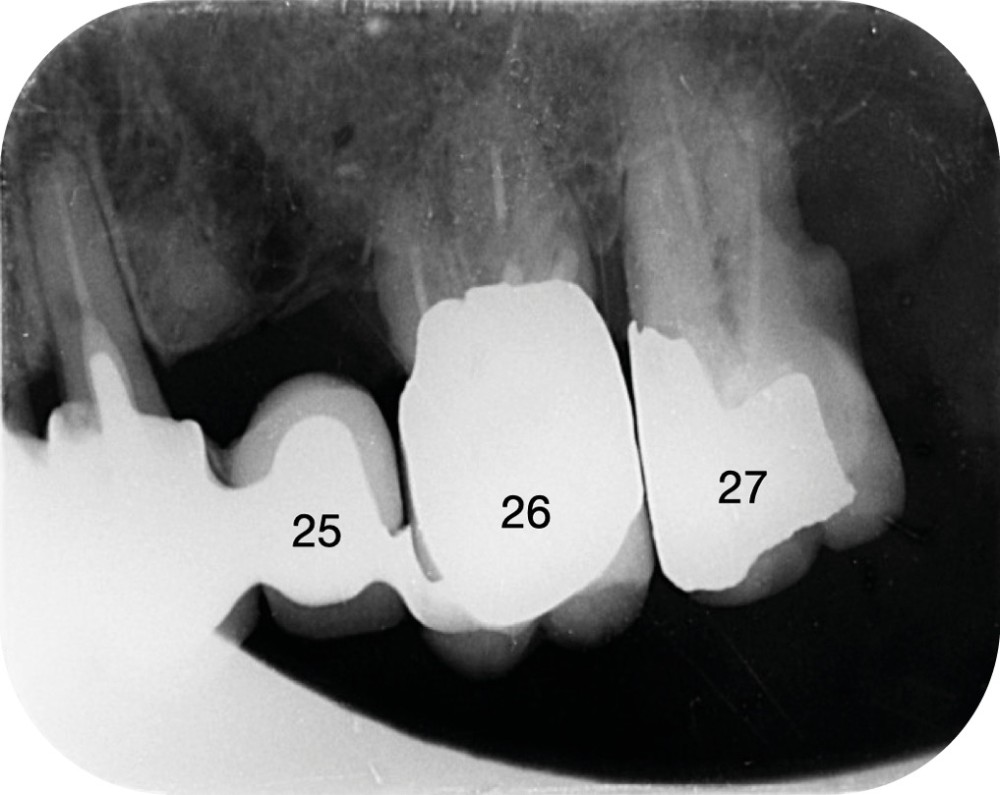

Au niveau du secteur 2, les dents 26 et 27 sont couronnées, fortement égressées, avec des atteintes parodontales terminales. La dent 25 est remplacée par un pontique en extension distale depuis un bridge dento-porté 13-23.

Concernant le secteur 2, le site 25 présente une crête osseuse fine nécessitant une régénération osseuse guidée (ROG) afin de pouvoir poser un implant dans de bonnes conditions (fig. 1).

La zone distale (26–27) offre un volume osseux important lié à l’égression des molaires, secondaire à la perte ancienne des molaires antagonistes.